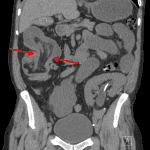

- Ileocolic intussusception extending to the hepatic flexure with upstream mild dilation of multiple fluid-filled loops of small bowel, measuring up to 4.2 cm in diameter

- Ileocolic intussusception

Ileocolic intussusception extending to the hepatic flexure with associated small bowel obstruction. In an adult, this finding raises concern for a neoplastic lead point. Recommend surgical consultation.